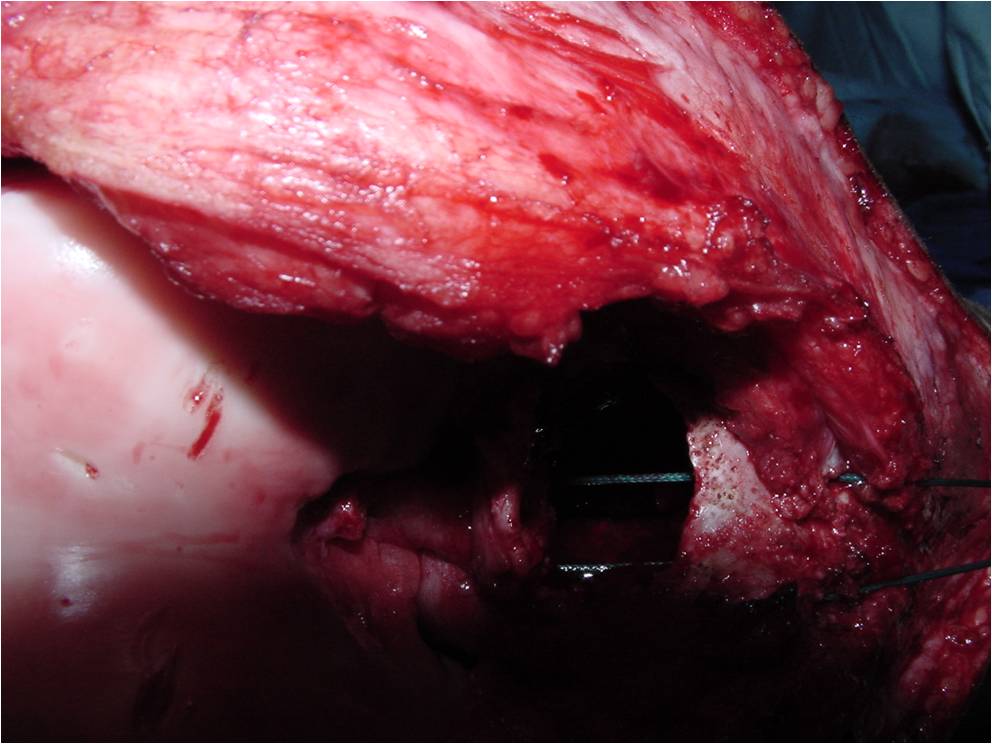

- Treatment of a Chondroblastoma of Proximal Humerus with Intralesional Curettage Resection, Cryosurgery and Bone Grafting

- intralesional curettage resection and bone grafting most common treatment

- Cement and internal fixation may also be used to fill the defect after removal for selected patients

- Local adjuvants such as cryosurgery (liquid nitrogen application) may be considered to decrease the risk of local recurrence